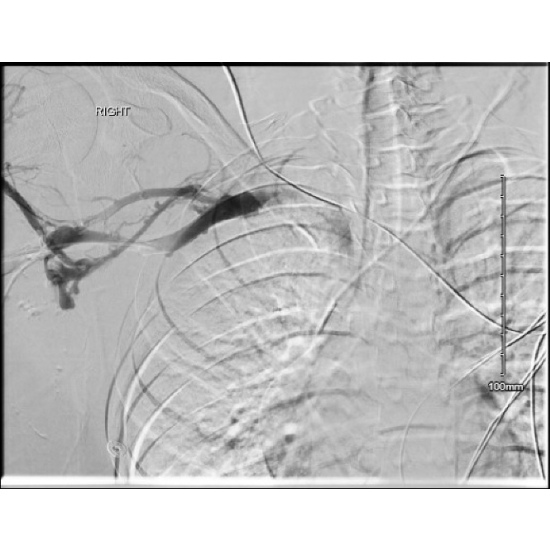

Peri-operative right upper extremity venogram demonstrated a complete occlusion of the right brachial, axillary, & subclavian veins. Large collateral from brachial to basilic vein, which appeared to drain the majority of the right upper extremity. Patent superior vena cava & right internal jugular.

Post-Angio Subclavian 1

Case Photo #6